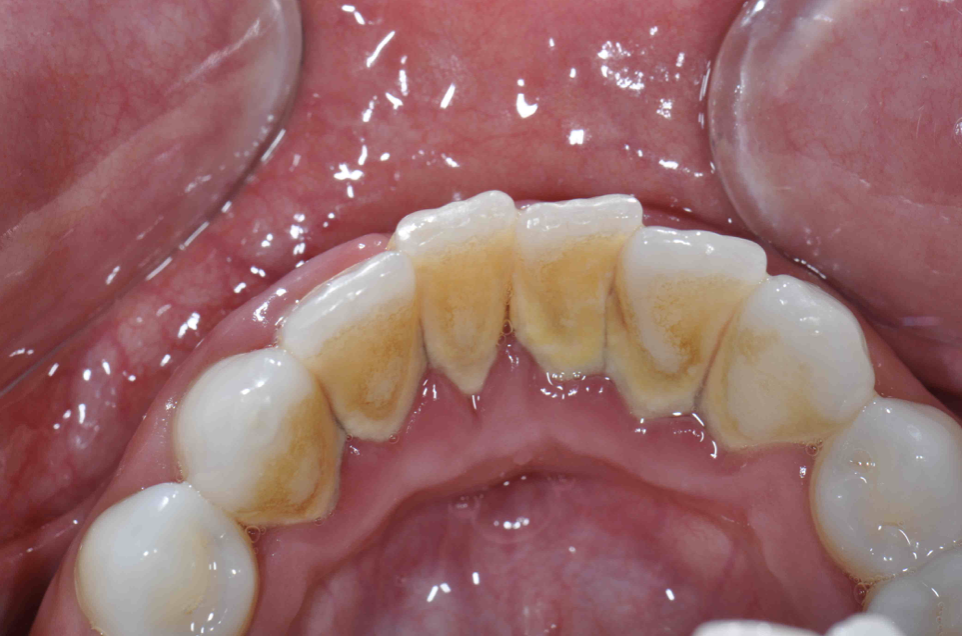

Fig 1. Extra-oral photography. All dental practices should provide the patient with the following four extra-oral photographs: the close-up smile (Fig 1), the retracted smile (Fig 2), the upper arch (Fig 3), and the lower arch (Fig 4).

Figure 1

Extra-oral photography. Extra-oral photography is essential for giving patients a full picture of their smile and oral health status. This has been a challenge for most dentists over the past two decades because many cameras that have the capability of taking high-quality, fully focused images of the dental arch have been difficult to use and program and awkward to sterilize. Other dentists have limited their use of such cameras to the occasional cosmetic case. However, extra-oral photography should be provided for every patient. The use of such photography and the type of photographs taken can vary from office to office, depending on the patient flow and the availability and training of personnel at that particular office. Regardless of these variations, however, all dental practices should take the following four extra-oral photos: the close-up smile, the retracted smile, the upper arch, and the lower arch (Figure 1 through Figure 4).